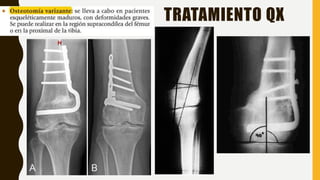

TRATAMIENTO Qx

• >10 años

• Genu valgo persistente.

• Distancia intermaleolar superior a 8

cm

• Ángulo femorotibial de más de 15 °

A)Tele-Rx de los miembros inferiores

Preoperatoria en la que se aprecia el valgo

bilateral, con ejes mecánicos que pasan por

la zona +3; los ángulos anatómicos

femorotibiales son de 29,3º en el miembro

inferior derecho y de 29,8º en la izquierdo.

A B

B)Tele-Rx de los miembros inferiores 1 año

después de la cirugía en la que se aprecian

las placas en “8” en ambos fémures. Los

ejes mecánicos pasan a través de la zona

+1/+2, y los ángulos anatómicos

femorotibiales están corregidos (8,3º el

derecho y 9,5º el izquierdo).

29,3º 29,8º 8,3º 9,5º